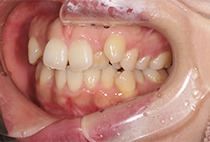

出っ歯と前歯のガタつきにお悩みだった20代女性の症例です。

金属アレルギーがあるため、メタルフリーで治療できる【インビザライン】による抜歯矯正を選択されました。

矯正治療2年6ヶ月

インビザライン、インプラントアンカー、美容治療